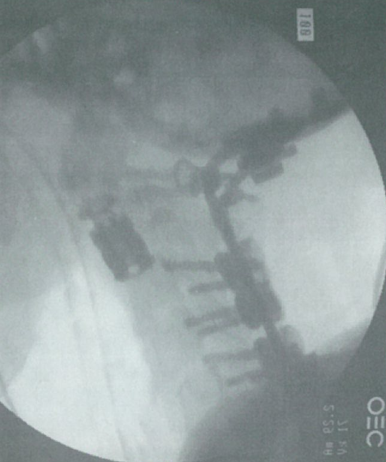

图1 C2椎体位置植入VBR钛笼。切除C2椎体,植入VBR钛笼。后方行枕骨-C5固定。